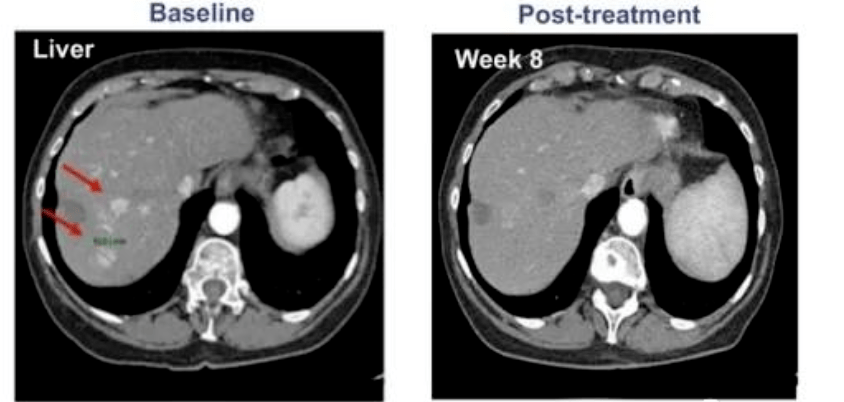

所有 9 名患者均接受了手術(shù)、常規(guī)放療和化療,但出現(xiàn)了失敗或不耐受。在接受最高劑量治療的 4 名患者中,有 1 名患者病情完全緩解。CT 掃描顯示,患者體內(nèi)所有病變均已消失,完全緩解后半年多沒(méi)有復(fù)發(fā)!